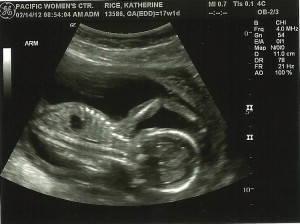

Other Goodness: Baby’s heartbeat was 169 beats/minute. And more ultrasound photos…

Baby Milestones: Baby is practice breathing and swallowing. According to the ultrasound, baby weighs about 7 oz.

Love that last ultrasound pic, too, just adorable!